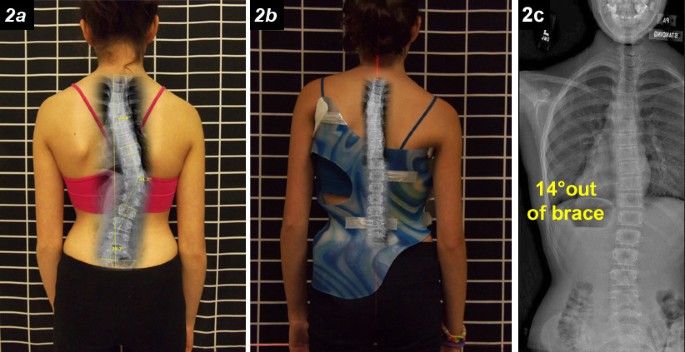

1. درجة التصحيح داخل الحزام (In-brace Correction)

أحد أقوى المؤشرات على نجاح العلاج هو مدى تحسن زاوية كوب أثناء ارتداء الحزام مباشرة.

فكلما كانت زاوية الانحناء داخل الحزام أصغر، زادت فرصة السيطرة على الجنف على المدى الطويل.

بعبارة بسيطة:

إذا لاحظ الطبيب تحسنًا واضحًا في الأشعة داخل الحزام، فذلك مؤشر إيجابي قوي للأهل.

هل الأشعة داخل الحزام مهمة؟

نعم، فهي من أقوى المؤشرات على نجاح العلاج مستقبلًا.